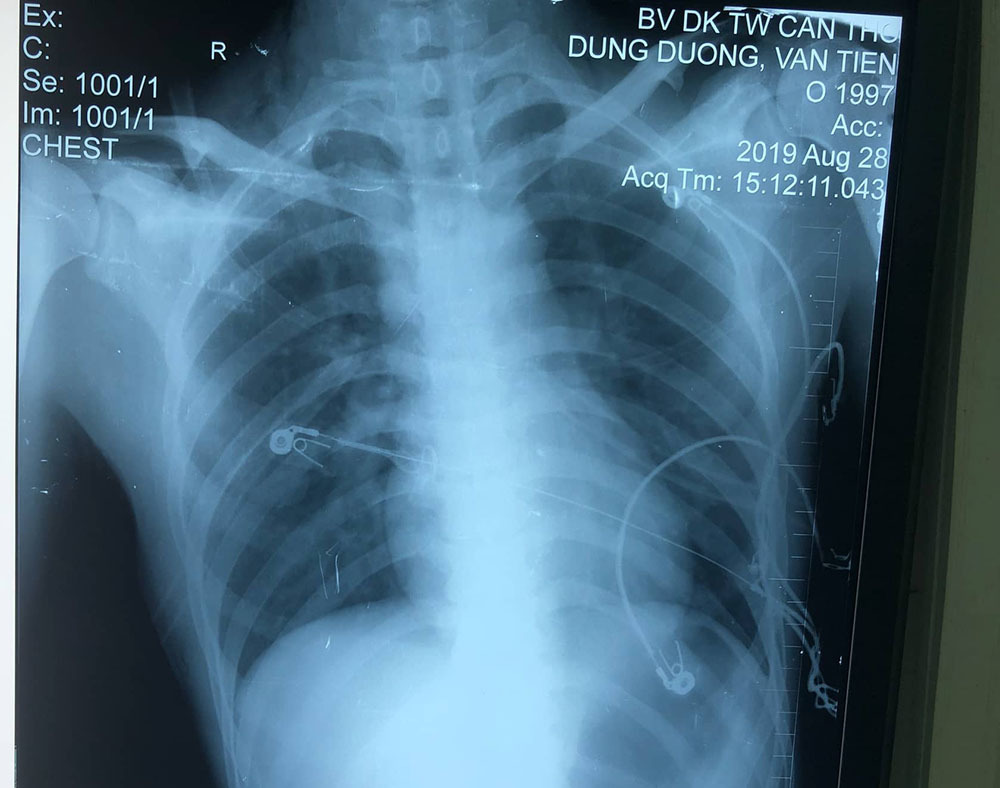

Người nhà bệnh nhân cho biết trước đó Dũng bị bạn dùng cây sắt đâm vào cổ, ngực, lưng và được đưa vào cấp cứu tại Bệnh viện huyện Long Mỹ. Kết quả chụp X-quang phát hiện thấy dị vật cản quang ở lồng ngực, tràn khí màng phổi hai bên nên đã được băng bó sơ cứu và chuyển tuyến lên Bệnh viện Đa khoa trung ương Cần Thơ.

Bệnh nhân được thực hiện các xét nghiệm, kết quả X-quang tim phổi thẳng cho thấy: một dị vật cản quang từ vùng cổ phải xuyên xuống đoạn gian đốt sống D3/D4, tràn khí màng phổi hai bên.

Hình chụp Xquang sau khi rút thanh sắt. Ảnh: Vietnamnet |